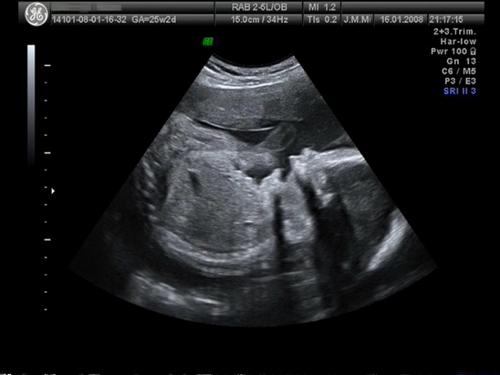

Taak jak obiecałam: oto moja mała ziewająca, chyba lekko znudzona albo śpiąca gwiazdeczka (miała prawo bo to już 21.00 godzina była) :-) podczas ostatniego usg w 25tc :tak:

Załączniki

• do forum.jpg

do forum.jpg

17,8 KB · Wyświetleń: 73